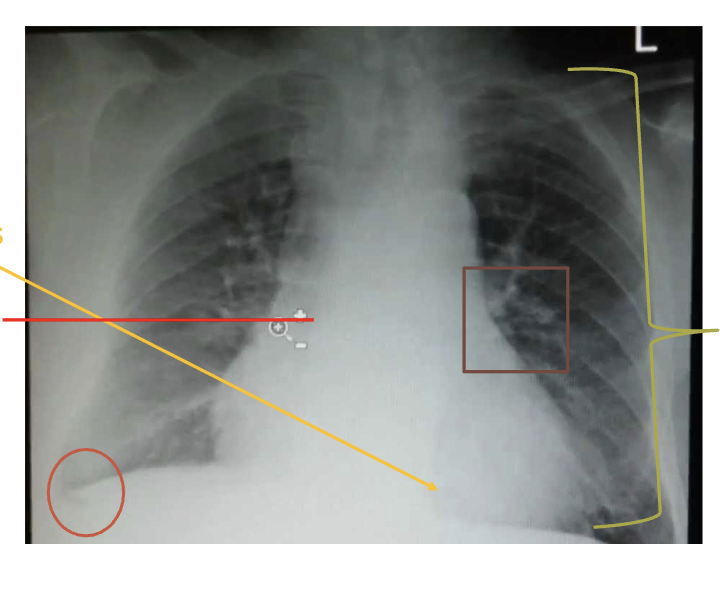

what can be look at to assess breathing in CXRs?

lung expansion/volume (should count 10 rubs posterior rib bilaterally), if one lung is larger than the other and are there areas of density, look at the crisp costophrenic angles - trace the lateral margins of lung to costophrenic angle. should look at the hemidiaphragms, and the cardiac borders (should be able to clearly see the L and R heart borders)